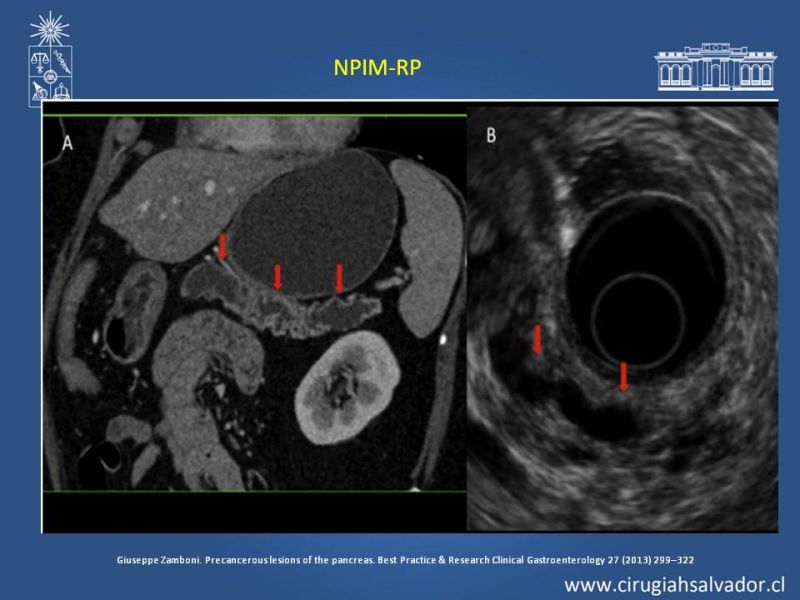

Neoplasias Quísticas Pancreáticas